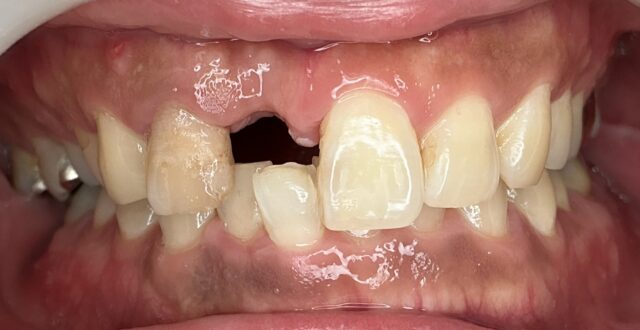

前歯インプラント

BEFORE

AFTER

症例情報

通院時の年齢

40代

性別

男性

通院目的

右上1の破折と右上2の審美障害

処置内容

右上1はインプラント補綴、右上2は補綴処置を行いました。

費用

約55万円

初診時